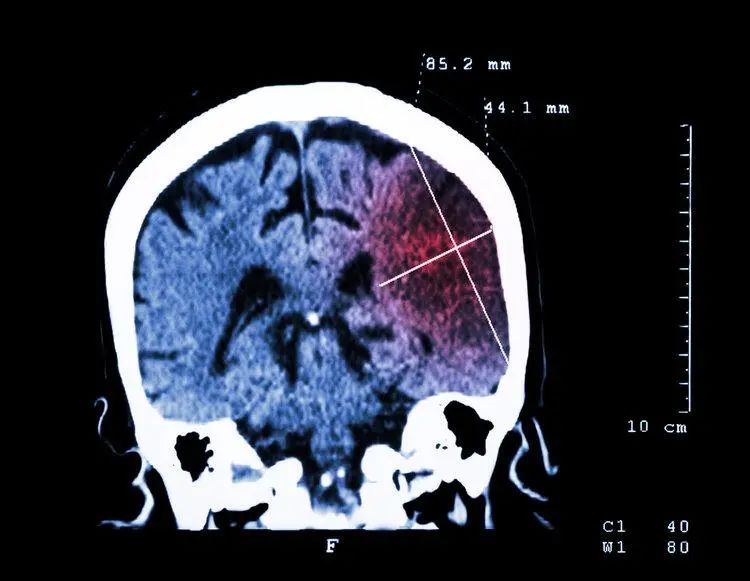

脑卒中分为缺血性脑卒中(脑梗死)和出血性脑卒中(脑出血),临床上超70%的卒中都是属于脑梗。脑梗被称为脑梗塞、缺血性脑卒中,是指多种原因导致脑部血液循环障碍且局部脑组织缺血、缺氧性坏死,从而出现了相应神经功能缺损的一种综合征。